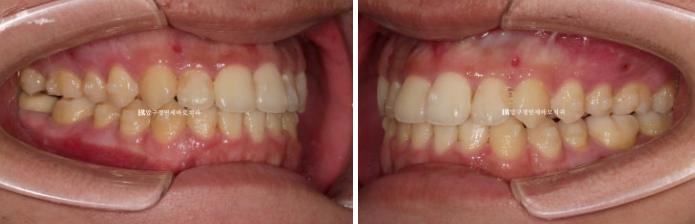

23.07~24.12

왼쪽은 초진이고, 오른쪽은 술전교정 마지막 모습입니다.

처음에 비하면 위 아래 앞니 간격이 오히려 더 커진 것 같은데요?

라고 말하실 수 있습니다.

술전교정에서는 주걱턱이 더 심해져 보이는 방향으로 치아를 움직여서 양악수술 직전 상태는 가장 부정교합이

심하고 불편한 상태가 됩니다.

그래야 수술 결과가 좋습니다.